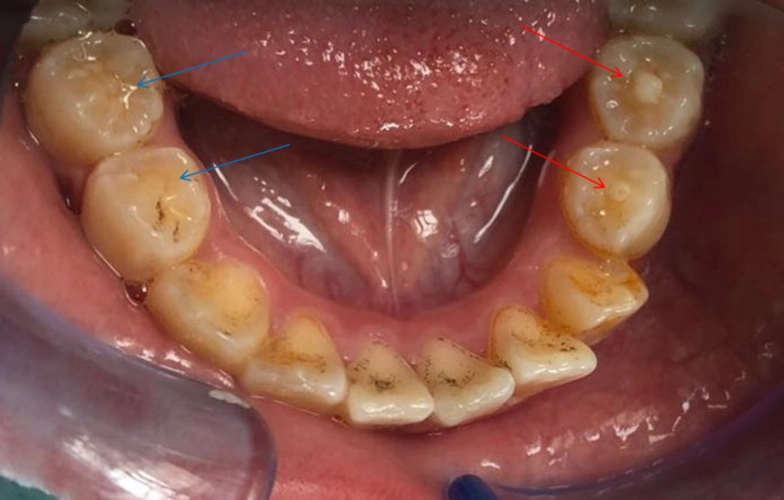

孩子新换的后牙中间多了一个尖_腾讯新闻